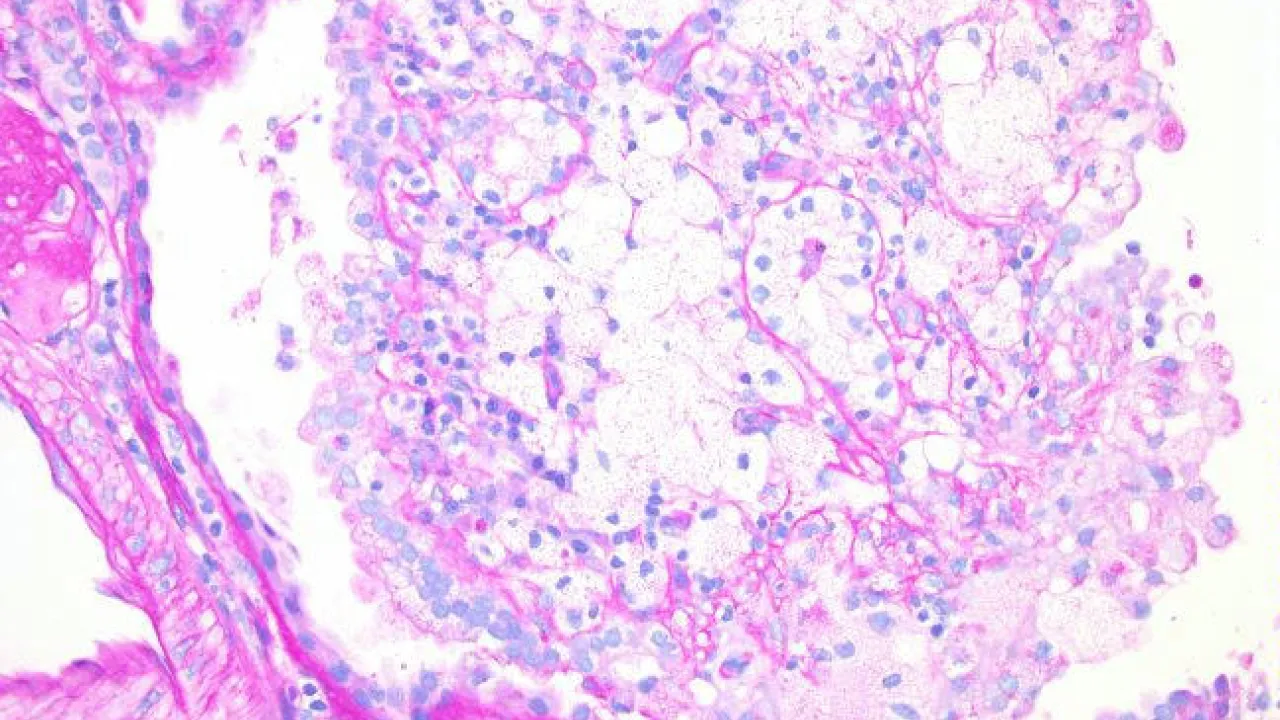

Kidney, Xanthogranulomatous pyelonephritis, PAS stain

Kidney, Xanthogranulomatous pyelonephritis, Trichrome stain